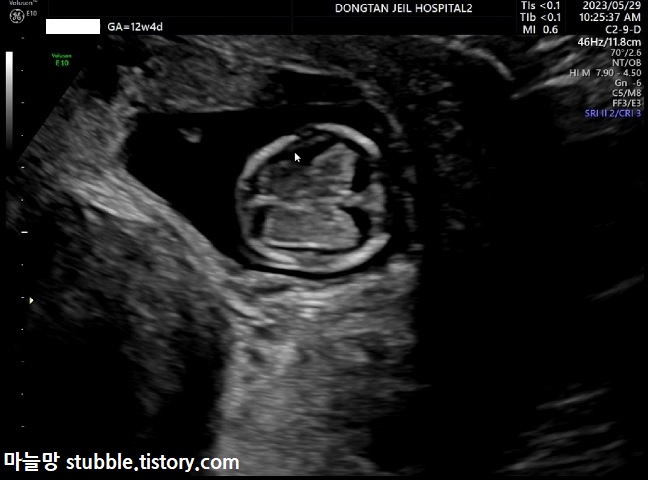

그럼 오늘 본 초음파중에 하이라이트만 정리해 볼게요.

12주 정밀 초음파에서는 아기의 뇌가 나비모양으로 잘 형성되고 있는지를 보았어요. 대칭이 되면 좋다고 하는데 초음파 각도에 따라 다르게 보여요.

또렷해진 사람의 모습! 많이 컸지요?

이번에는 얼굴 쪽 옆모습을 잡았습니다.

얼굴이 거의 사람의 형태입니다.

다운증후군의 경우 코뼈가 안 생기는 경우도 있다고 하여 코뼈를 확인합니다.

우리 아기는 코뼈도 잘 생겨 있었어요.

코뼈의 길이(NBL)는 2.67mm입니다.

그리고 12주 4일의 첫 입체 초음파입니다.

팔을 쭈욱 펴서 자궁벽을 안고 있는 우리 아기의 모습입니다.

얼굴은 옆을 보고 있어요.

아기 등 쪽은 태반이라고 하네요.

생각보다 앙상한 우리 아기